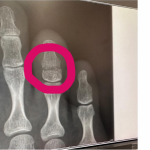

骨折した右足でハイキックするRENA©️RIZIN